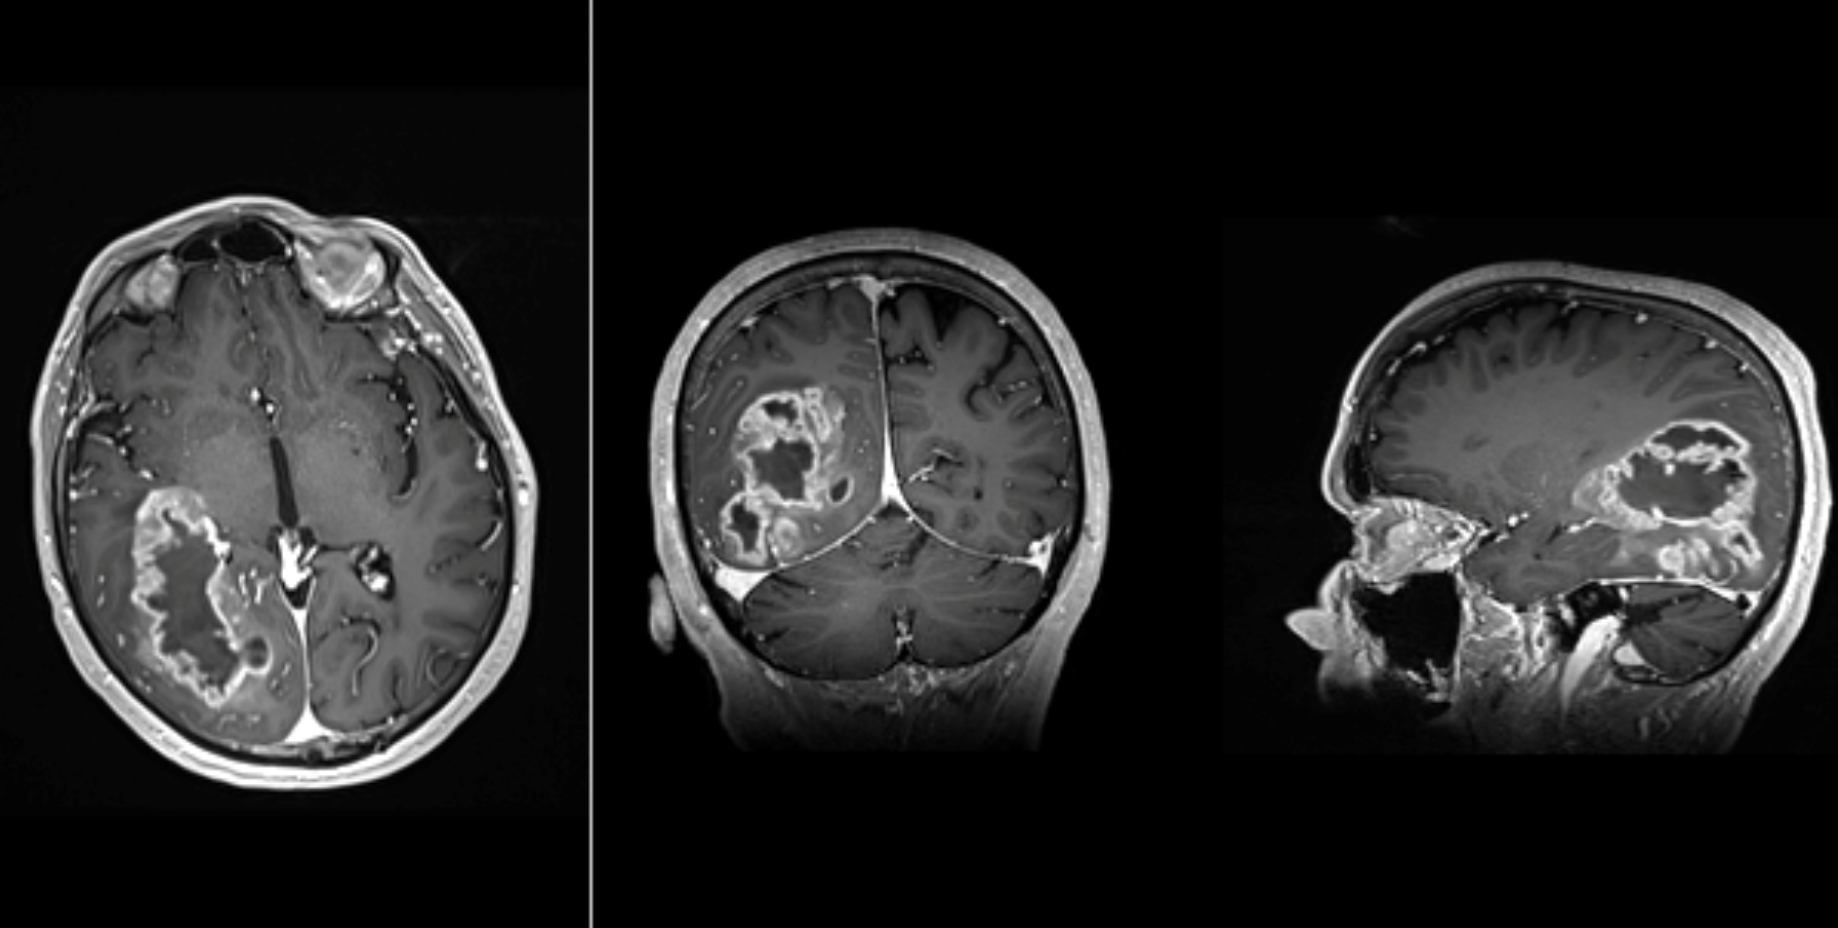

- RMN cerebral cu substanță de contrast

- Imagistică avansată